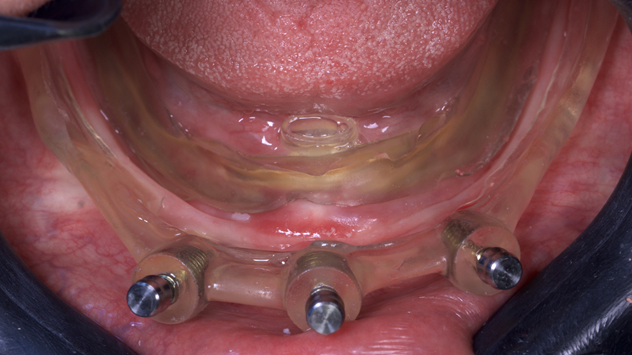

O guia foi fixado após estabilização em oclusão com a prótese superior. Após a retirada do guia de oclusão, foi fixada a guia de fresagem e instalação dos implantes, que foram instalados com torques superiores a 32N, o que permitiu a captura imediata da prótese provisória através do pilar de titânio e resina de fluxo.